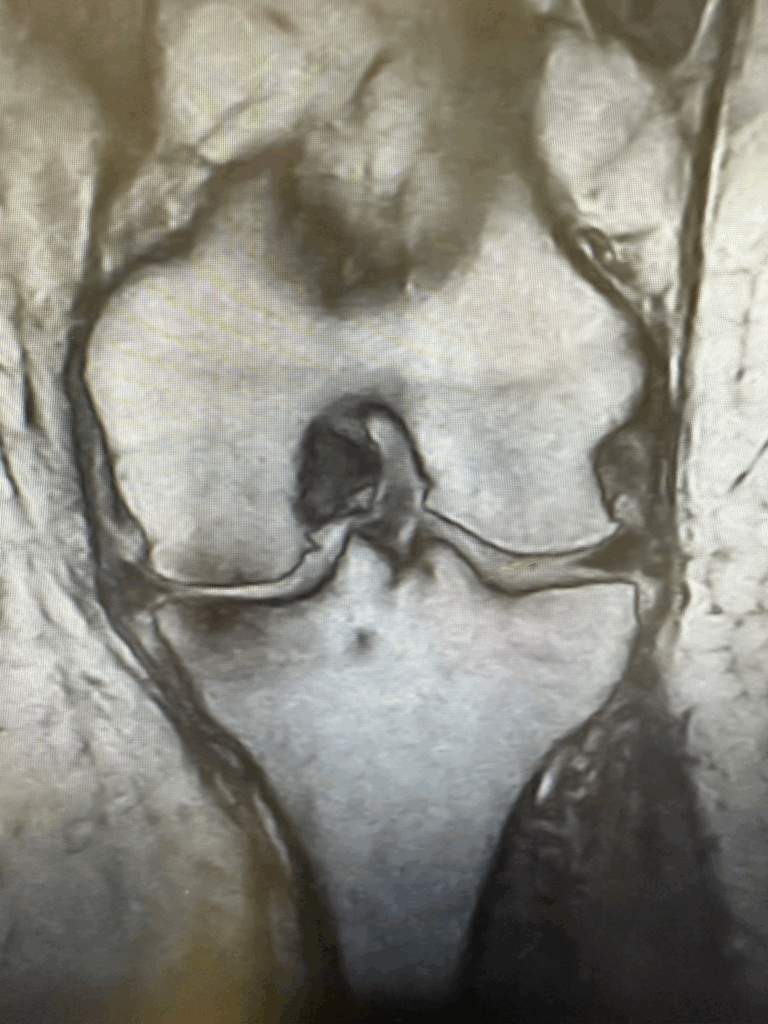

- Risonanza magnetica: per l’artrosi è un esame di secondo livello, utile nei casi selezionati per analizzare i tessuti molli: menischi, legamenti, cartilagine e tessuto osseo cellulare